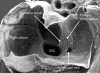

This scanning electron micrograph is from a mouse heart at a slightly earlier stage of development than the human embryo shown in fig 6. The atrioventricular canal has been dissected away from the atrial chambers, permitting the atrial cavities to be photographed from beneath. The valves of the systemic venous sinus have now formed, showing that the sinus itself (SVS) opens exclusively to the right side of the primary atrium. Note that the orifice of the pulmonary vein now opens inferiorly to the left side of the atrium. The primary atrial septum is growing as a shelf between the systemic and pulmonary venous orifices. Note also the bulge at the right side of the pulmonary venous orifice, between it and the opening of the systemic venous sinus. This is the “spina vestibuli” initially described by His,9 which we term the vestibular spine.

Figure 9

This higher power scanning electron micrograph shows the atrial roof, prepared in comparable fashion to fig 8, but at a slightly later stage of development. The upper margin of the primary atrial foramen has now broken down to form the secondary interatrial foramen (double headed arrow). Note the mesenchymal cap on the leading edge of the primary septum, which is growing towards the atrioventricular endocardial cushions, carrying forward the inferior end of the orifice of the systemic venous sinus (star). The upper end of the orifice becomes the septum spurium in the roof of the right atrial appendage.